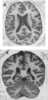

Localized cerebral atrophy